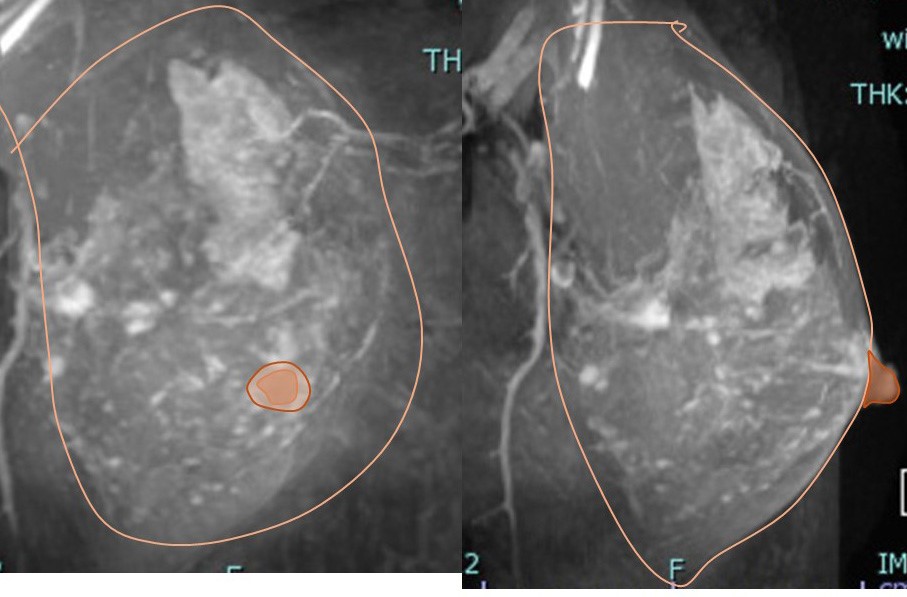

1. 画像所見

MMGで壊死型石灰化の範囲は68mm MRIでの拡がり

3. 病変に対する(マージンをつけた)切除範囲